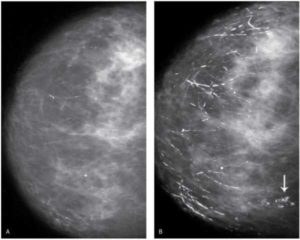

Чтобы исключить патологию, назначается проведение ультразвукового исследования (УЗИ) или маммографии. Если обнаруживаются уплотнения или узелки, женщину направят на дополнительное обследование. Обязательно исследуется кровь.

Обычно данный процесс диагностируют при проведении УЗИ или маммографии, поскольку выраженной клинической картины фиброзно-жировая инволюция не имеет.

Наиболее эффективным методом диагностики инволюции признают рентгенографическое обследование. Оно позволяет обнаружить недуг в 97% случаев.

- УЗИ-диагностика не информативна и может пропустить мелкие фиброзные образования. Более точные данные даст рентгенография молочных желез.

• Доли 1 и 2 типа называются девственными. Чаще всего они встречаются у девочек и еще не рожавших женщин в молодом возрасте.• 4 тип включается в этот процесс позже, в период лактации. Благодаря долям 4 типа молочные железы увеличивают выработку сначала молозива, а потом переходного и зрелого грудного молока.Постепенно, по мере угасания гормонов железистая ткань замещается жировой. В постклимактерическом периоде она исчезает полностью, остаются только жировые клетки. Вот и вся суть обратной эволюции. Как правило, на нижних участках молочных желез изменения проходят интенсивнее, что приводит к нежелательным последствиям: грудь теряет форму и провисает. При низком гормональном уровне инволюция может вступить в активную фазу и в 40 лет, а когда климакс не спешит заявлять о себе, грудь может оставаться в хорошей форме даже после 50-ти. Иными словами, здесь все индивидуально и обусловлено особенностями организма.• После 50-ти инволюционные процессы значительно усиливаются, УЗИ показывает заметную разницу в количестве железистой и жировой ткани в пользу последней.• К 55 годам жировые клетки почти полностью вытесняют железистую ткань.Для определения инволюции медики используют два распространенных метода: ультразвуковое исследование и маммографию. Если результат не позволяет максимально точно оценить состояние, назначается комплексное обследование. Это значит, что к повторному проведению маммографии и УЗИ добавляется еще ряд исследований: инфракрасная галактография, термография, компьютерная томография и анализ крови.Фиброзно-жировую инволюцию, появившуюся в зрелом возрасте, медики не приравнивают к патологическим процессам. Они не видят в ней причины для проведения какого-то специфического лечения. Но возрастные изменения структуры молочной железы, как и любые другие перемены в организме, должны быть под постоянным контролем. Это необходимо для того, чтобы до минимума снизить риск возникновения онкологии.

В данном случае нужно проходить обследование УЗИ. Исследование молочной железы укажет на изменения в протоках желез. Жировая ткань довольно светлая и на снимках сосуды и молочные протоки хорошо заметны.